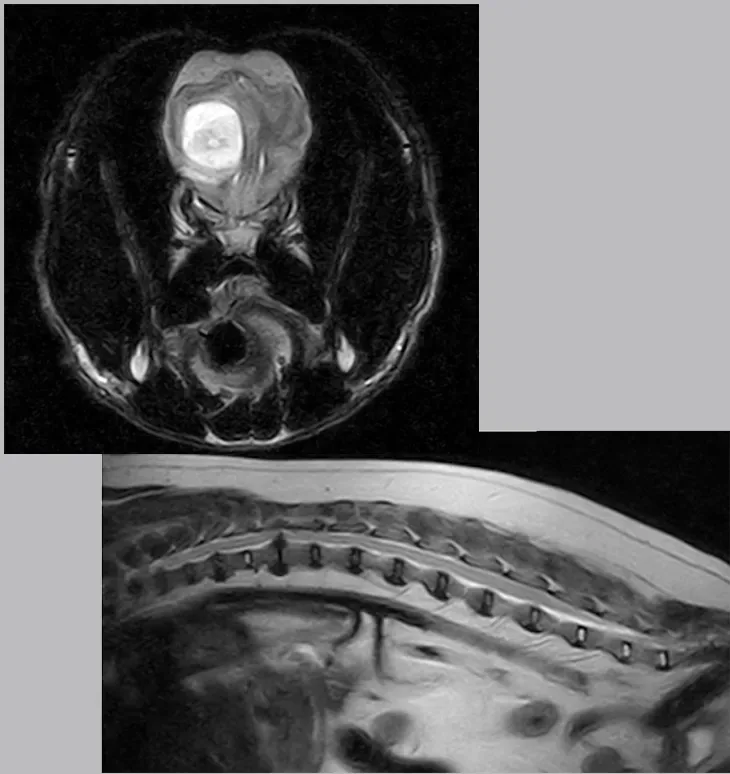

La risonanza magnetica (RMN) è la tecnica diagnostica più avanzata per lo studio del sistema nervoso centrale e di molte altre strutture interne.

Permette di individuare con straordinaria sensibilità lesioni dell’encefalo e del midollo spinale, come:

• Encefaliti e meningiti

• Emorragie o ischemie cerebrali

• Tumori del sistema nervoso

• Ernie del disco e patologie traumatiche

• Malformazioni congenite (come l’idrocefalo)

Negli ultimi anni, l’impiego si è esteso anche alla diagnosi di patologie articolari, muscolari e tendinee, ampliando le possibilità terapeutiche e riabilitative.